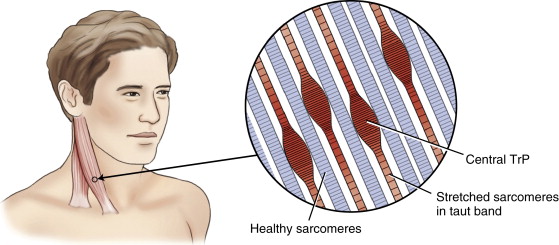

트리거 포인트(Trigger Point)란?

근막 조직 내의 특정 지점에서 발생되며, 근막이 서로 엉겨붙는 유착이라는 것이 발생한 상태입니다. 이 상태에서는 근육이 딱딱하게 뭉쳐져 있고, 민감해져 있는 상태, 즉 근육의 기능이 저하되어 있는 포인트입니다.

발통점이라고도 하며, 압박 또는 기타의 자극에 의하여 특수한 감각이나 증상을 일으킬 수 있는 신체 내의 특수한 곳입니다. 트리거 포인트가 있는 곳은 마치 매듭이 묶여있는 단단합니다.